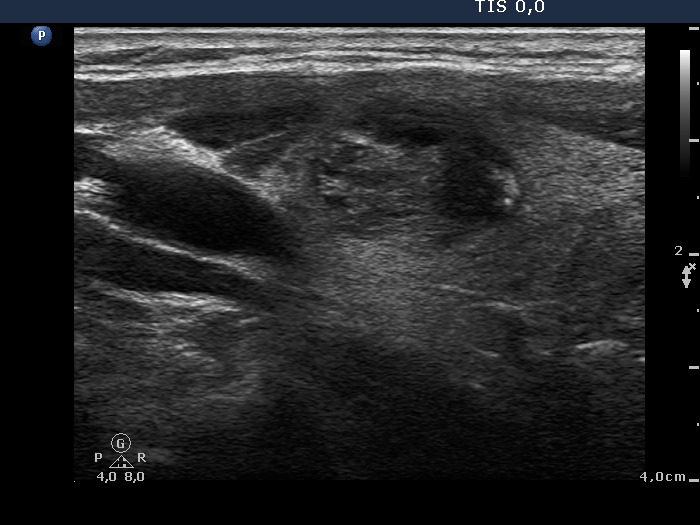

Benign hyperplastic nodule (histological diagnosis) - case 1091 |

Papillary carcinoma (histological diagnosis) - case 1731 |

Small granules dominate the nodule. At least two of them have dorsal narrowing tale. The remaining figures are similarly bright therefore these are very likely also comet-tail artifacts.

It is very difficult to categorize these figures. Considering the final diagnosis even the small pale figures might be punctate echogenic foci because there are no similarly pale lines. The two large bright granules are more typical forms of punctate echogenic foci. Note that there is a less hyperechogenic shadow not only dorsal but even ventral to the larger one. It means that this figure is not a comet-tail artifact but the granule is located in a minimally hypoechogenic parenchyma.